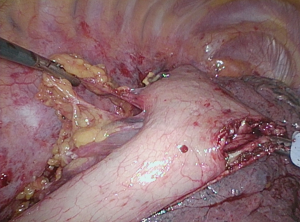

The gastrocolic ligament is then divided. This is facilitated by the operating surgeon gently grasping the anterior wall of the stomach with the left hand and elevating the stomach toward the hiatus while the assistant applies downward traction on the gastrocolic ligament near the edge of the transverse colon. This puts the gastrocolic ligament on some tension and helps to expose the right gastroepiploic arcade (Figure 3). Once the right gastroepiploic vessels have been identified, the division of the gastrocolic ligament is initiated usually at a point near the mid antrum. Dissection initially proceeds in a cephalad direction up the greater curvature to the level of the left gastroepiploic which is divided with the energy device (Figure 4). In overweight individuals, this part of the dissection can be challenging because of the amount of fat and one must proceed cautiously so as not to injure the splenic flexure.

Once the lesser sac has been entered, the stomach can be elevated away from the pancreas and retroperitoneum and adhesions divided sharply. Sometimes it is easier to visualize the right gastroepiploic arcade from the posterior aspect of the stomach as there may be less fat and the division of the gastrocolic ligament can be performed keeping the vascular arcade in view. To do this, the posterior wall of the stomach is grasped and elevated away from the pancreas and towards the hiatus and liver. Once the watershed between the gastroepiploic and the short gastric vessels has been reached, the division of the gastrosplenic ligament and the short gastric vessels is accomplished close to the gastric wall. This is facilitated by retracting the stomach to the patient’s right side putting the ligament on some tension (Figure 5A,B,C). Care must be taken to be sure that the jaws of the energy device are completely across each of the vessels, which are taken in sequence, partial division will result in hemorrhage. Elevating the stomach off the retroperitoneum and retracting the fundus to the patient’s right helps to expose the uppermost short gastric as well as the occasional posterior branch coming off the splenic artery. Once these vessels are divided, the fundus is completely mobilized off the retroperitoneum and the left crus (Figure 6A,B). The hiatus is then entered medial to the left crus (Figure 7).